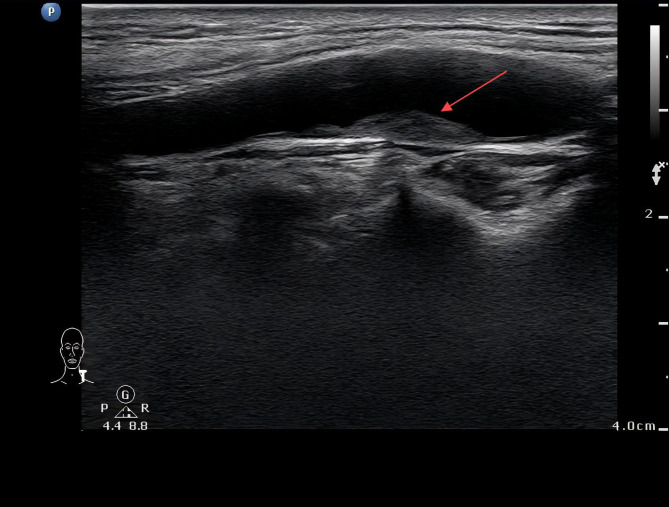

Methods: A total of 838 patients with carotid plaques receiving lipid-lowering therapy were enrolled between July 2020 and May 2024 and followed up for 12 months. Carotid ultrasound was performed at baseline and follow-up to evaluate plaque characteristics. Plaque regression was defined as meeting any of the following criteria: (1) reduction in plaque area ≥ 5%, (2) decrease in plaque thickness ≥ 0.4 mm, or (3) reduction in plaque number, as assessed by vascular ultrasound imaging. Plaque echogenicity was classified into three types: hypoechoic, hyperechoic, and mixed echogenicity. Cox proportional hazards regression analysis was performed to assess the association between plaque echogenicity and plaque regression, adjusting for potential confounding factors.

Abstract Image